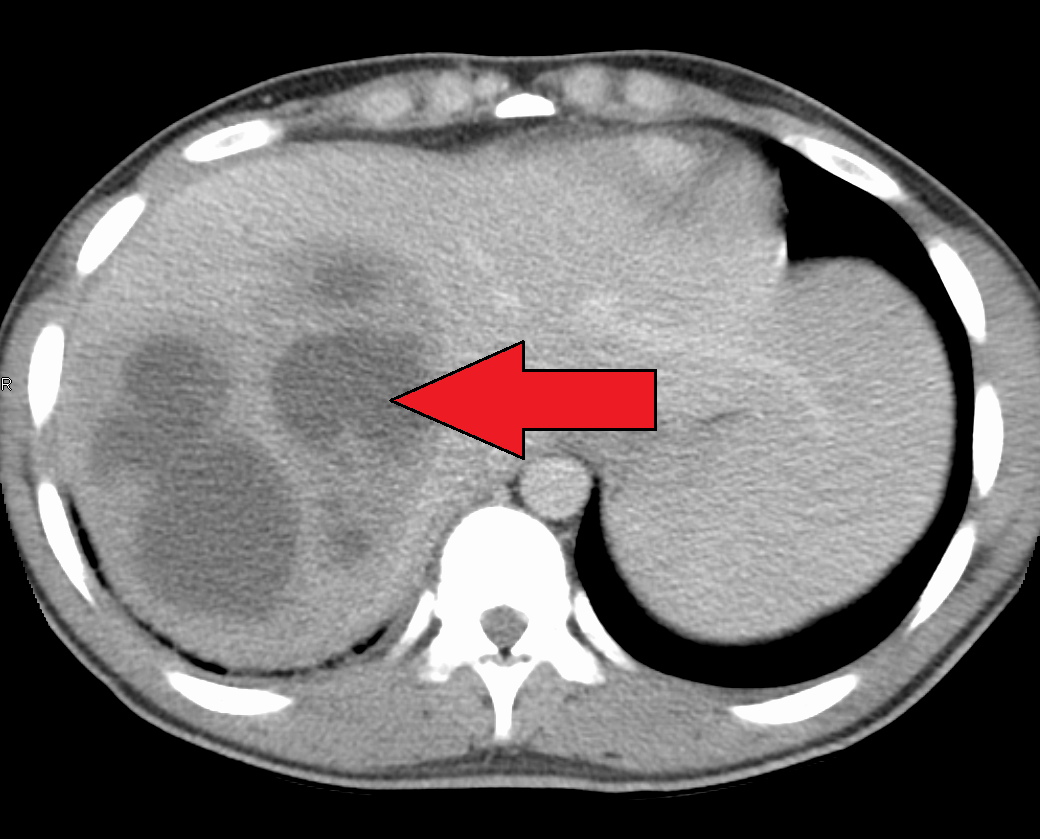

Symptoms of liver abscess may include: Chest pain (lower right) Pain in the right upper abdomen (more common) or throughout the abdomen (less common) Clay-colored stools. Dark urine. Fever, chills, night sweats. Loss of appetite. Nausea, vomiting. Unintentional weight loss.